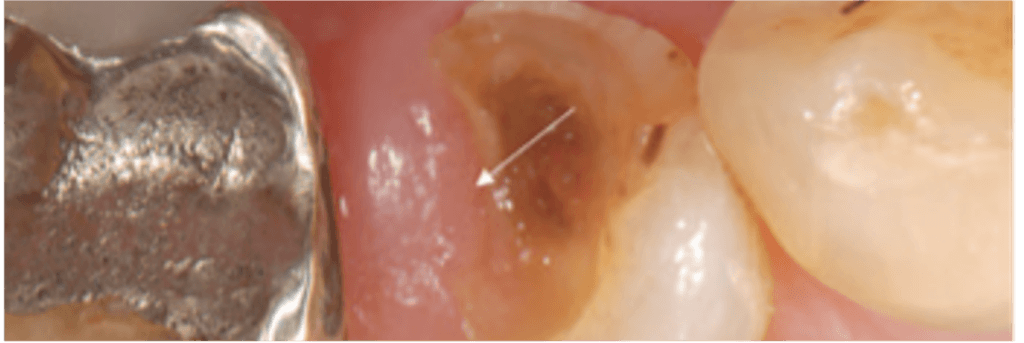

A cross-sectional survey with dental practitioners, members of the National Dental Practice-Based Research Network in the United States included a clinical scenario, with a radiograph and a photograph from a published study1 (Figure 1, used with permission1). Members of the network were invited to participate via email and the survey was open from Nov 18 until Dec 17, 2021. The data were collected through a web survey in Constant Contact, a digital and email marketing platform. Data were analyzed using descriptive statistics.

The case was described as follows: “An adult patient presents with restoration loss on the mandibular right premolar. Upon clinical and radiographic examination, you diagnose superficial demineralized dentin reaching beyond the CEJ with the proximal margin partially covered by overgrowing gingival tissue. The tooth is vital and there is no periapical radiolucency. What would be your most likely standard of care treatment approach for this case scenario in your practice?”

The responses for the clinical options to restore function are shown in Figure 1. Most practitioners chose “Core build up + Full Crown or Onlay” (63%). Only 1% would restore with amalgam.